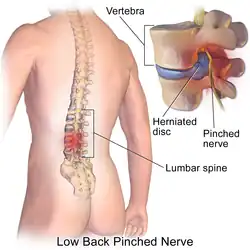

- Click images to see larger versions

-

Lumbar disc lesions, classification

Lumbar disc lesions, classification -

Illustration depicting herniated disc and spinal nerve compression

Illustration depicting herniated disc and spinal nerve compression -